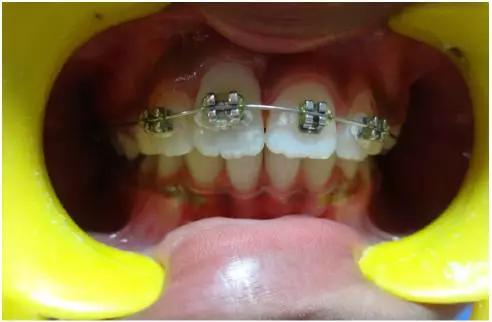

正畸牽引觀察其復(fù)位情況: 先觀察挫入的牙齒在未干預(yù)的情況下自發(fā)復(fù)位的情況。經(jīng)過3周的觀察,牙12復(fù)位,但牙11沒有顯示出復(fù)位的跡象。因此,使用MBT托槽正畸牽引牙11復(fù)位。為了讓其沿正確的方向復(fù)位,使用橡皮圈以獲得緩慢持續(xù)的牽引力(圖3)。

(圖3)

正畸牽引5周后,牙齒復(fù)位到其原始位置,與其他切牙完全對(duì)齊(圖3)。開始嘗試血運(yùn)重建。重新打開根管,使用次氯酸鈉和生理鹽水沖洗。然后插入無菌根管銼,并將其推到根尖處,以使血流進(jìn)入根管。一旦血液到達(dá)釉牙骨質(zhì)界,放置一個(gè)濕潤的無菌棉球靜置15分鐘,直到血凝塊形成,再放置約2-3mm的MAT在血凝塊上。在MAT上覆蓋一個(gè)濕棉球,隨后進(jìn)行臨時(shí)修復(fù)。以后再替換為玻璃離子水門汀墊底和復(fù)合樹脂修復(fù)。復(fù)診時(shí)間為1、3、6、9和12月。正畸復(fù)位保留12周。然而,在這么長的保留期內(nèi)還是復(fù)發(fā)了錯(cuò)位,這也強(qiáng)調(diào)了在嚴(yán)重侵入的情況下長期復(fù)位的重要性,因?yàn)槔奂暗难例X周圍出現(xiàn)大量的牙槽骨喪失(圖 4)。